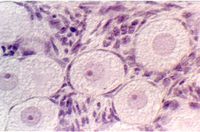

The uterus is a muscular sac, lined with epithelium that undergoes cyclic changes. The wall is made up of thick smooth muscle, organized in interlacing bundles that run randomly. It is called the myometrium In the above photograph, the uterine glands (a part of the endometrium) are seen as straight tubular glands leading to a main lumen. This is diagnostic of the early stage of the cycle or the Proliferative phase. What hormone is secreted by the follicle during this early stage of the cycle?

As stated above, the uterine lining consists of glands that are called "endometrium" As the ovary and oviduct are undergoing changes with the cycle, the uterine lining is being prepared to receive an embryo. The normal human menstral cycle is divided into three phases by the hormonal events and changes in the uterine lining. The first phase is called the Proliferative phase. This coincides with the rise in estrogens early in the cycle and is distinguished in the uterus by lengthening endometrial glands.

Slide 86 shows a uterus in the proliferative phase. The endometrium is illustrated in the photograph below. Note that the cells are low columnar to high columnar. The glands are relatively straight with a narrow lumina. Outside the glands is the highly cellular lamina propria. The following photos illustrate the proliferative phase with higher magnifications.